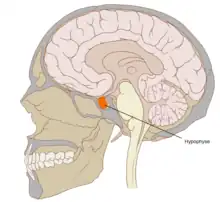

Located at the base of the brain, the pituitary gland is protected by a bony structure called the sella turcica of the sphenoid bone. | |

In humans, the pituitary gland rests upon the hypophyseal fossa of the sphenoid bone, in the center of the middle cranial fossa. It sits in a protective bony enclosure called the sella turcica, covered by the dural fold diaphragma sellae.[3]

Location of the pituitary gland in the human brain

Location of the pituitary gland in the human brain Pituitary and pineal glands